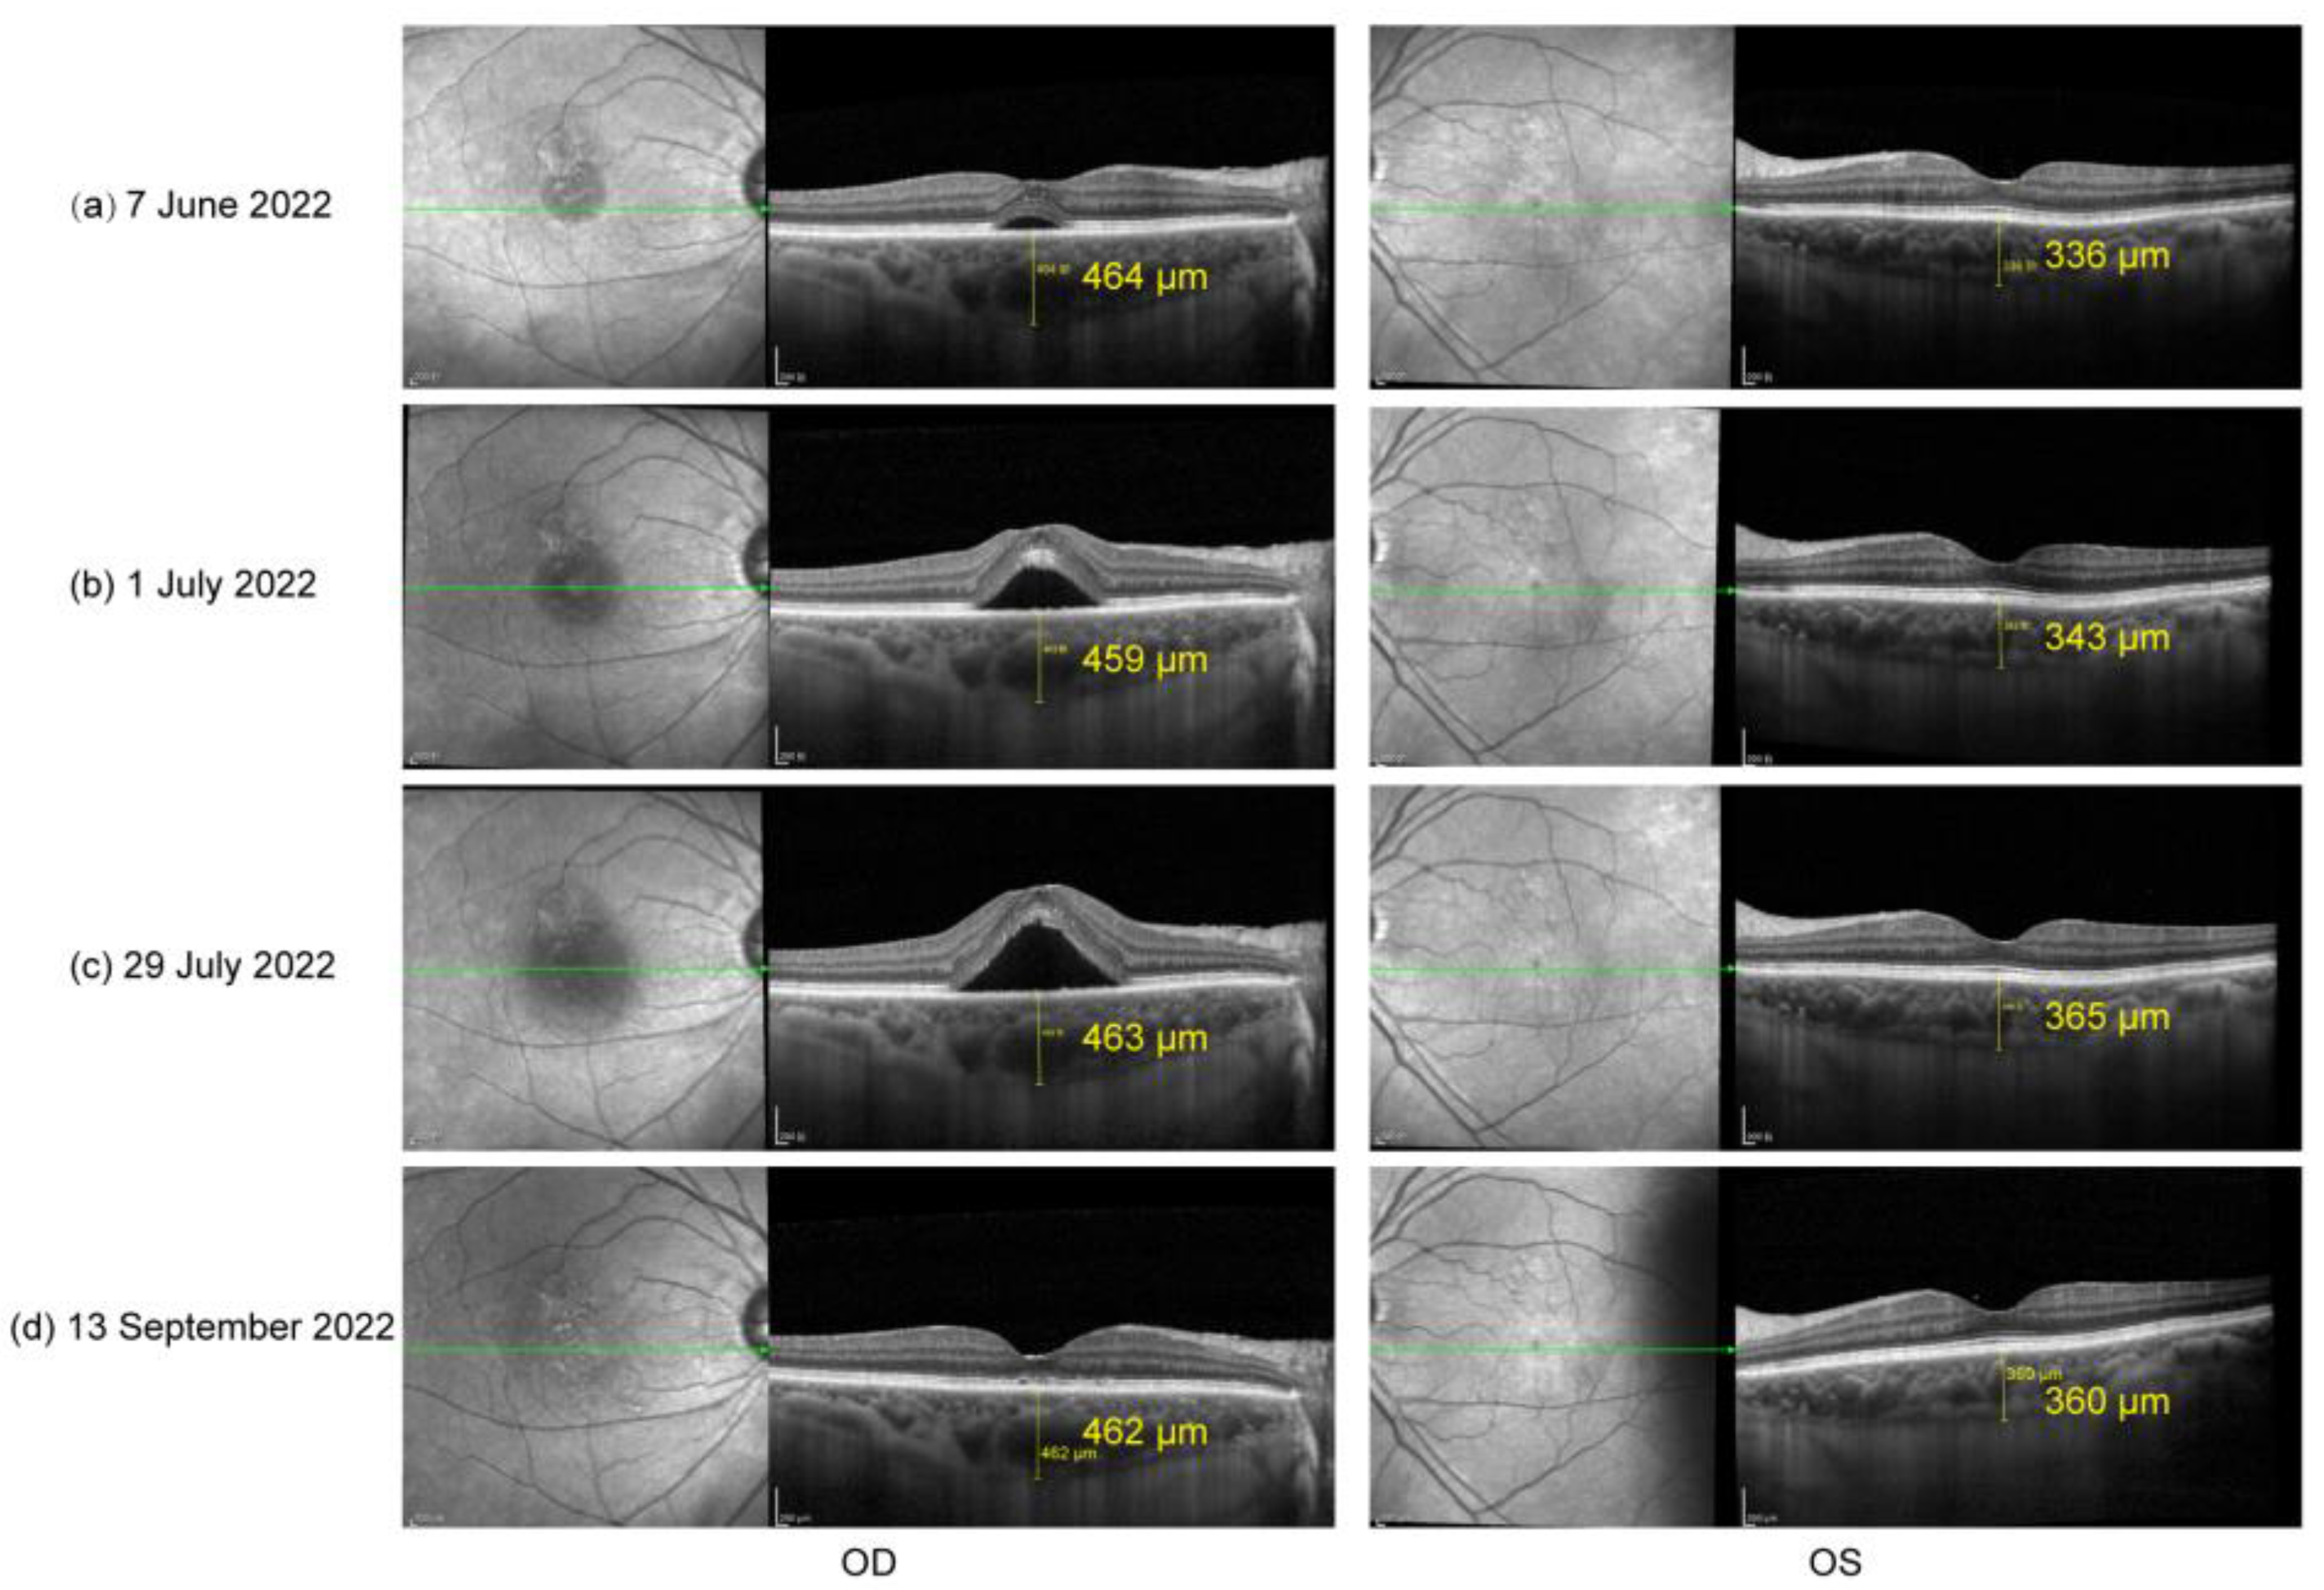

The patient did not show up until 3 and a half months later (7 June 2022) due to the COVID-19 pandemic in Shanghai. His oral prednisone dose had been tapered to 20 mg (qd). He complained about slightly blurred vision in both eyes (20/25 in OD and 20/22 in OS). A slit lamp examination presented few cells in vitreous body OU and sub-macular fluid OD. EDI-OCT showed sub-macular fluid OD and an increase in choroid thickness OU (Figure 2a). The condition was considered a relapse of inflammation. Thus, the patient was given 30 mg (qd) of oral prednisone and 125 mg (bid) of cyclosporin. Improved BCVA, 20/22 in OD and 20/20 in OS, and clear vitreous body a week later indicated the relief of inflammation. However, in the following observations (1 July 2022 and 29 July 2022), the retinal fluid in his right eye gradually increased (Figure 2b,c) without any sign of activated inflammation and quiet anterior and posterior segments were observed in his left eye. A dilated fundus examination revealed a depigmented fundus appearance and sub-macular fluid in his right eye (Figure 3a). Indocyanine green angiography (ICGA) (Heidelberg Engineering, Heidelberg, Germany) of the right eye showed the focal dilation of choroidal veins and delayed perfusion in the early phase (Figure 3d). Hyperfluorescent spots and patches with slight leakage were superior to the fovea, which showed strengthened fluorescence in the late phase. Fluorescein angiography (FA) (Heidelberg Engineering, Heidelberg, Germany) demonstrated that the hyperfluorescent patch superior to the fovea gradually leaked over time and displayed strengthened fluorescence in the late phase (Figure 3d). OCT revealed subretinal fluid in fovea and the irregular RPE, suspected RPE break, and the elongation of photoreceptor cells segments in the region of serous retinal detachment (Figure 3b,c). Complicated central serous chorioretinopathy (CSC) in his right eye was diagnosed, and the tapering of oral prednisone by 5 mg a week was set. Additionally, the patient was given one micropulse laser treatment. One and a half months later (13 September 2022), subretinal fluid was completely absorbed (Figure 2d).

Figure 2.

(a) OCT on 7 June 2022: sub-macular fluid OD and increase in choroid thickness OU; (b) OCT on 1 July 2022 and (c) OCT on 29 July 2022: significantly increased sub-macular fluid OD; (d) OCT on 13 September 2022: completely absorbed subretinal fluid.

Numerous risk factors have been outlined in developing CSC, including the use of local and systemic steroids [25,26,27,28,29,30]. The high-dose use of corticosteroids was suggested to damage the posterior blood–ocular barrier [25], though the precise mechanisms are largely unknown. Recently, Zhao et al. provided evidence demonstrating that glucocorticoids may bind the mineralocorticoid receptor (MR) and activate the MR signaling pathway, resulting in choroidal enlargement [31]. Treated with a specific MR antagonist, patients with chronic non-resolved CSC have shown the impressive and rapid resolution of retinal detachment and choroidal vasodilation, as well as improved visual acuity [31]. However, one study showed that steroid-induced CSC may be an idiosyncratic response in selected vulnerable individuals rather than a dose-dependent effect [32]. The researchers measured the choroid thickness in 18 patients systemically treated with a high dose of corticosteroid (19.5 ± 4.1 mg/kg per day). The mean subfoveal choroidal thickness at baseline was 259.8 μm and showed no significant change at 1 day, 1 week, or 1 month after steroid administration. Only one patient who had presented with pigment epithelial detachment and a thick choroid (381.1 μm) developed bilateral CSC. In our case, after the complete resolution of active inflammation, the choroid thickness of the patient’s right eye was still as high as 393 μm (25 February 2022), which could be considered a pachychoroid. After another 3-month treatment of oral steroids, the choroidal thickness of his right eye was increased to 464 μm and the choroidal thickness of his left eye was also slightly increased (from 326 to 336 μm), which might be explained by MR signaling pathway activation [31]. Thus, we consider that pachychoroid and systemic steroids might have together contributed to the development of complicated CSC in our case. We recommend that ophthalmologists pay attention to the possible ocular side effects of systemic steroids, especially in eyes with a pachychoroid.